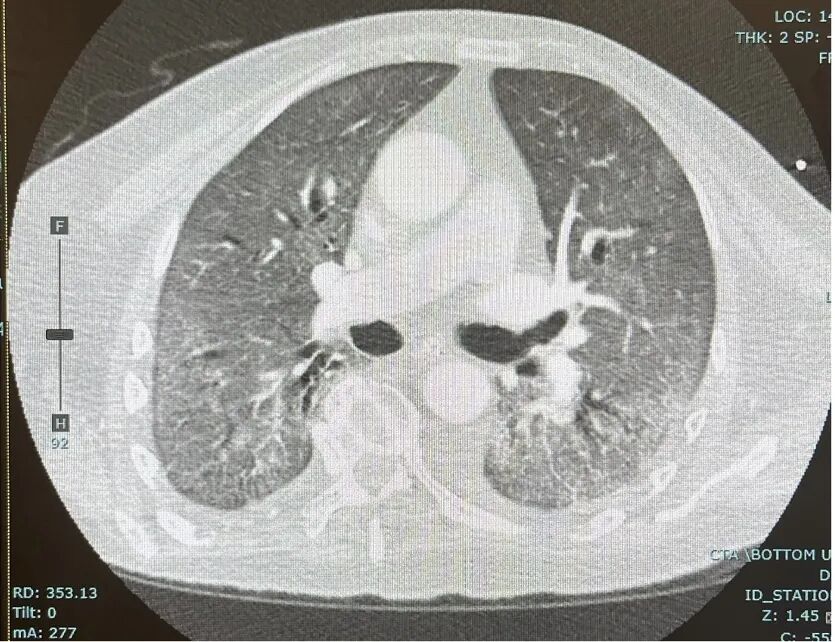

回到病例,突然缺氧患者必须要做CTPA,排除肺栓塞。栓塞倒是没有,可现在的肺野影像是这样的:(图5)

图5:肺水肿CT影像

与前面(图1)我所选的影像对比可以看到,现在的特征仍然是毛玻璃影,但是却是同质的毛玻璃影,不是片状的,而且整个两侧肺野都是这样,另外,在下肺野处明显有六角线出现,术语为小叶间隔增厚,表示淋巴液流量增加。在这种情况下,基本上可以根据这份CT确定是「肺水肿」的情况。肺水肿怎么来的?要做一些分析:1、前24小时的输入量和输出量,这位患者的输入量是1.7升,为了做CTPA、为了保护肾脏,又给了另外500毫升生理盐水点滴,整体的净输入量大概是2.2升。